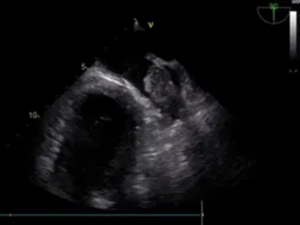

经食道超声左心耳

血栓